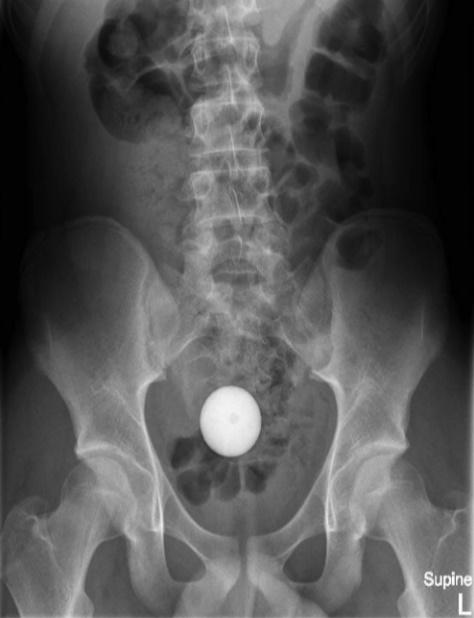

報告指出,這名少年將高爾夫球塞進自己的肛門,惟愈塞愈深,最後竟塞進腸道,雖然少年指無感到劇烈疼痛,但眼見自己已無法處理,只好向母親求助前往就醫。少年指出,雖然球球跑進體內,但他並沒有感受到劇烈疼痛感。X光顯示,一顆球體就在腹腔內。醫生決定先後使用醫療網、導管、吸引器等6種方法,希望將高爾夫球取出但失敗,折騰了2小時後,醫生亦要暫停休息。

X光顯示,一顆球體卡在腹腔內。(外科病例報告) X光顯示,一顆球體卡在腹腔內。(外科病例報告)